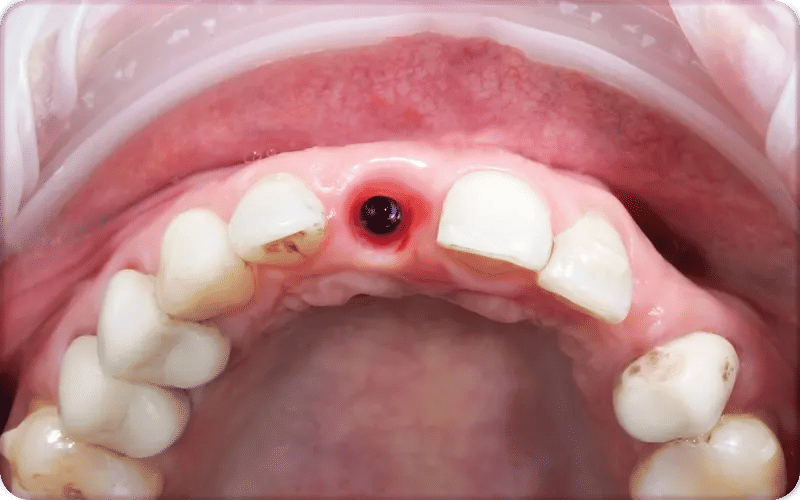

Before and After Bone Loss Bad Dental Implants Pictures

5. Visible issues in scans or images (bad dental implants xray / bad dental implants pictures): X-rays or clinical photos may reveal bone loss, poor placement, or structural failure not visible to the naked eye.